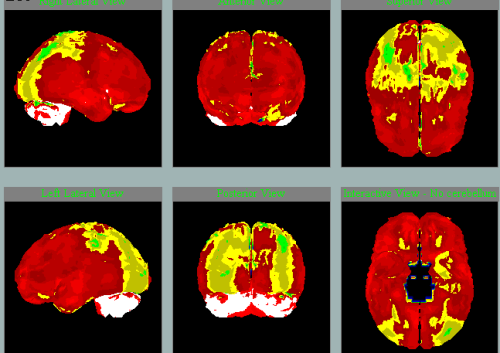

Takto na SPECT mozku zpracovaném NeuroGamem vypadá:

Normální perfúze